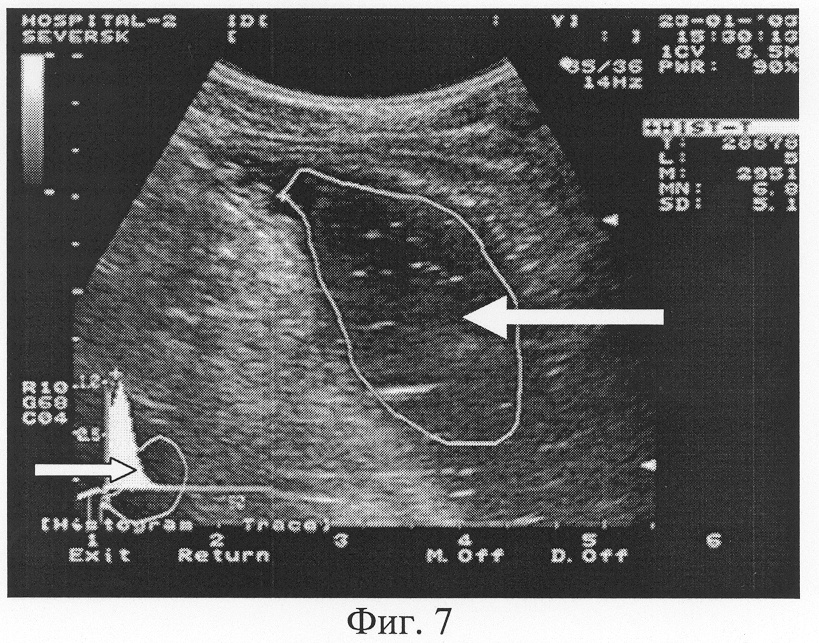

Для подсчета коэффициента эхогенности проводится процедура гистографического исследования содержимого желудка, которая аналогична анализу гистограммы содержимого двенадцатиперстной кишки. Технически заключается в построении фронтального либо косого ультразвукового срезов содержимого желудка с целью эхолокации максимально возможного пространства органа. На зафиксированном ультразвуковом изображении выполняется гистография очерченной площади (функция аппаратов ультразвуковой диагностики) содержимого желудка без захвата в зону анализа стенок органа и окружающих тканей (Фиг.7, 8).

Фиг.7. Трансабдоминальное ультразвуковое исследование желудка. Гистографический анализ содержимого желудка с использованием зоны маркера в виде очерченной ее площади (обозначена стрелкой ). Значение показателя преобладающей эхоинтенсивности MN содержимого желудка составило 6,8 единицы (норматив 6-9 единиц). Графическая кривая гистограммы (обозначена стрелкой ) с острым пиком подтверждает факт однородного содержимого желудка. Отлично прослеживается поверхность слизистой и структура стенки желудка.